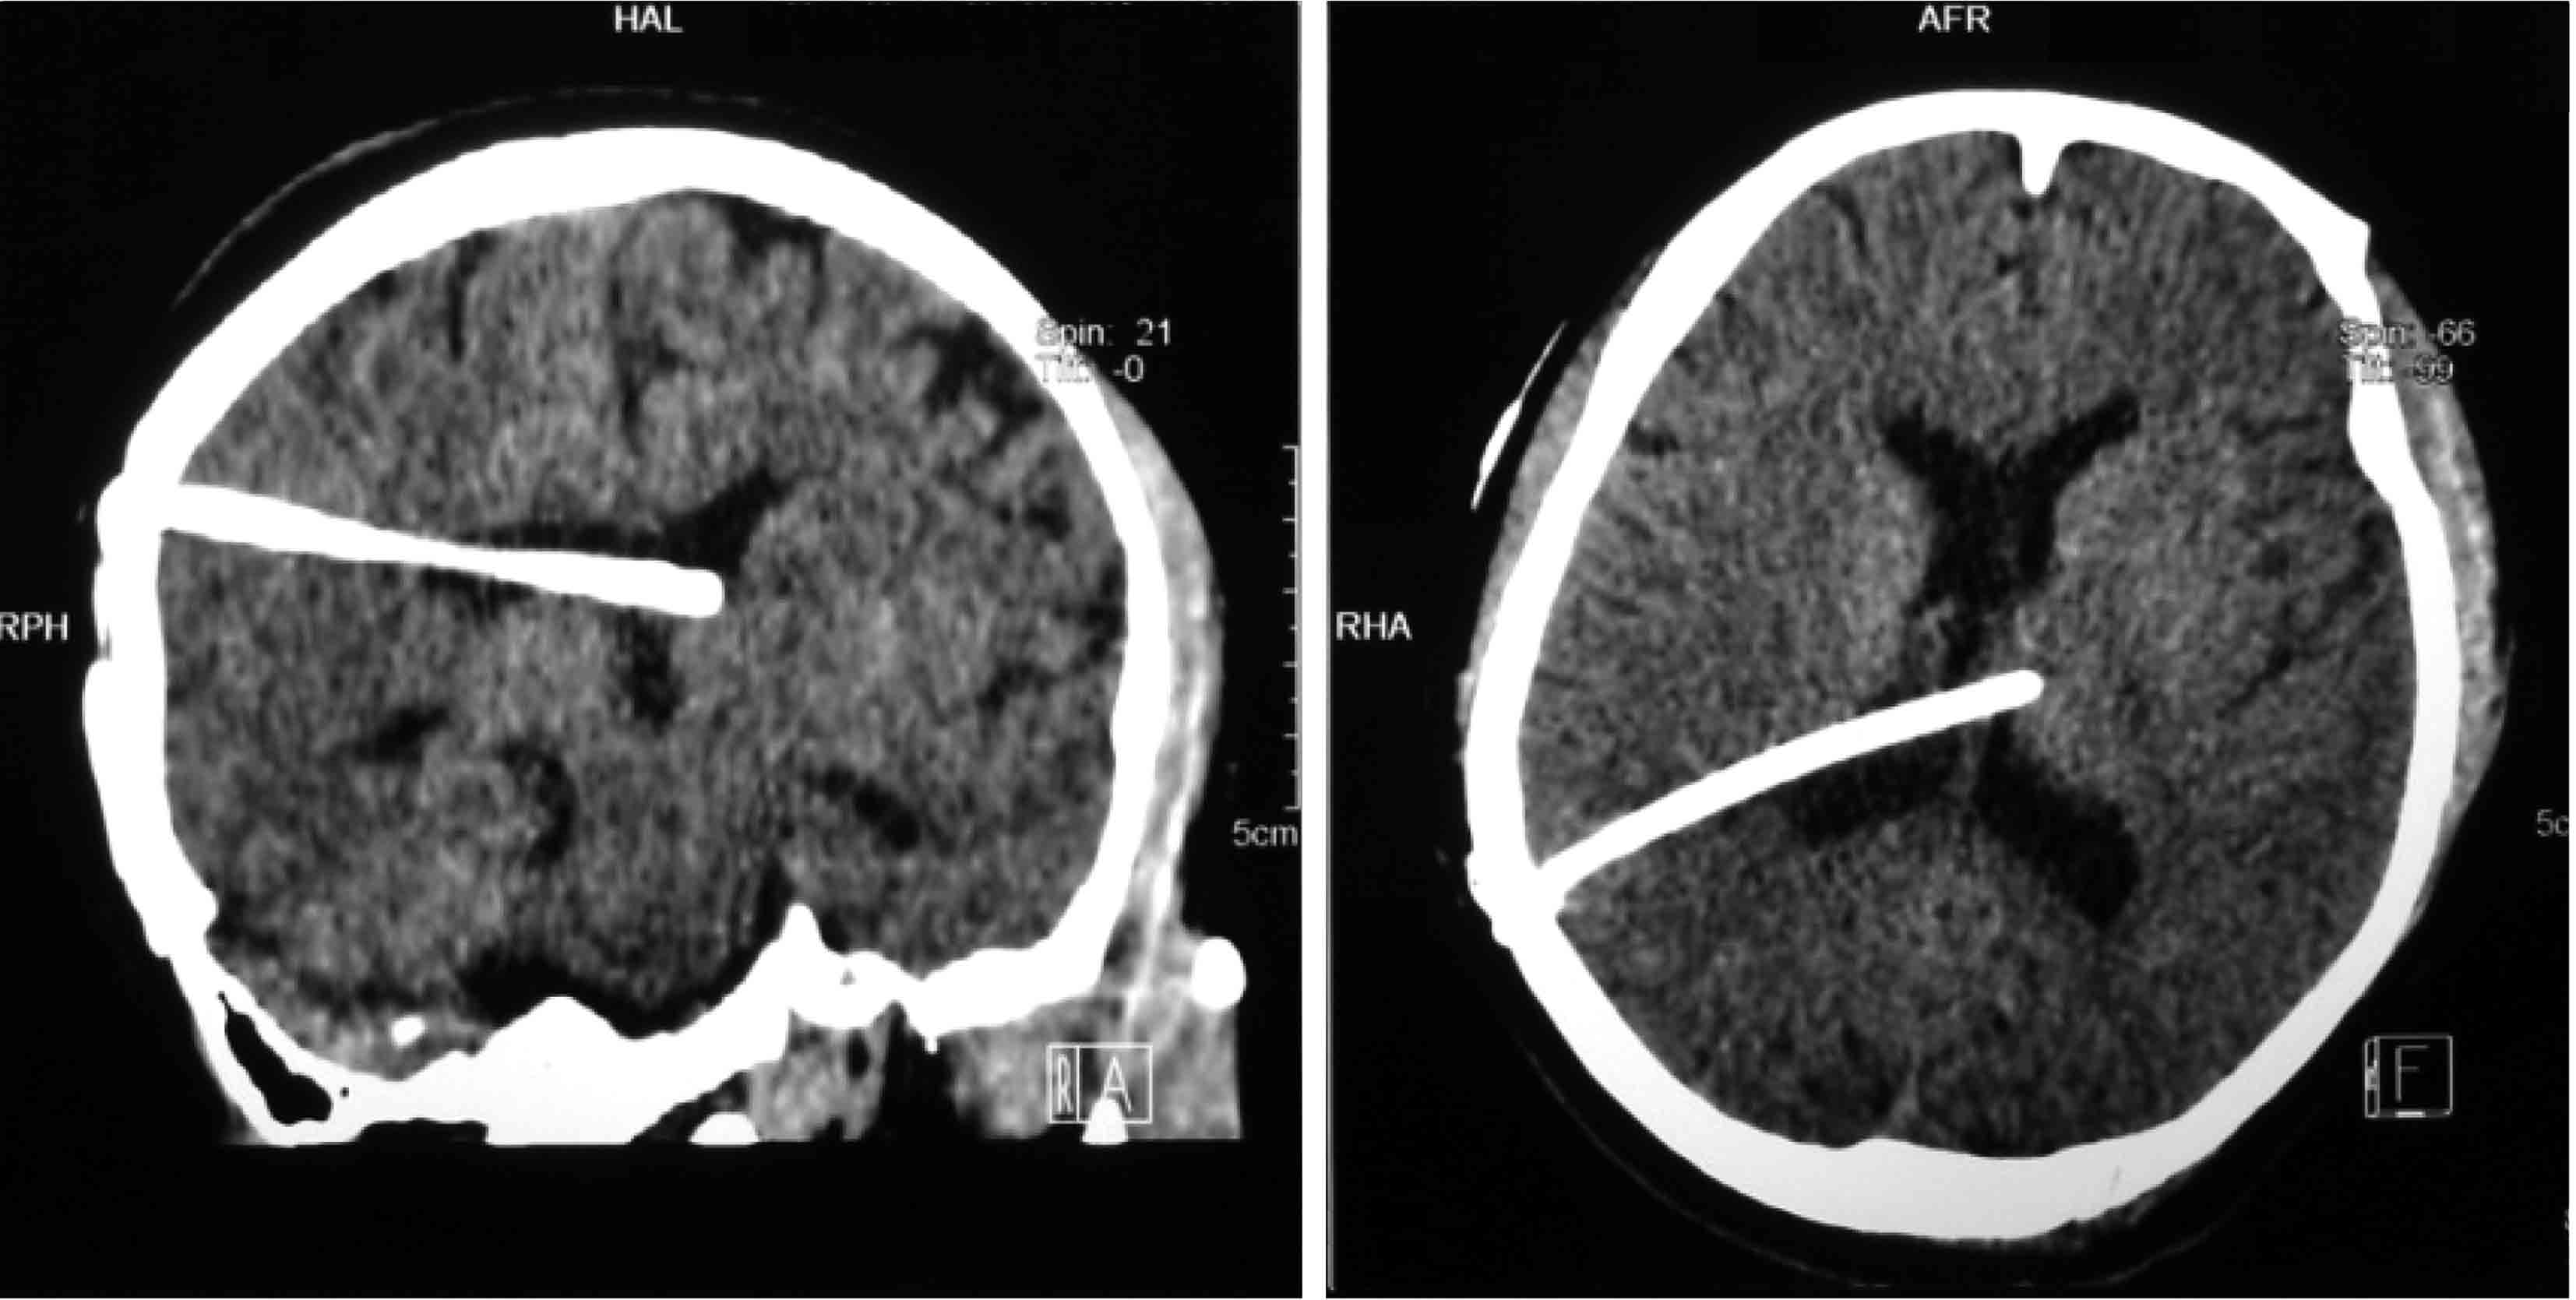

图3-1-4-2 脑室分流管的理想位置

a.CT矢状位见分流管位于侧脑室额角;b.CT冠状位见分流管位于额角略偏向中线;c.内镜下见分流管远端位于室间孔